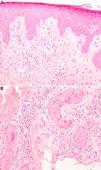

Physical examination revealed a square-shaped erythematous plaque (9×12cm) with well-defined borders and an eroded center (Fig. 1). The location coincided with one of the sites irradiated when the patient received a total dose of 7.8Gy in 3 separate procedures. Histopathology demonstrated hyperkeratosis, irregular acanthosis and dysmaturation of the epidermis, a moderate predominantly neutrophilic perieccrine inflammatory infiltrate in the dermis, and squamous metaplasia of both eccrine coil and duct (Fig. 2). These findings were compatible with ESS.

A, Hyperkeratosis and irregular acanthosis. Signs of epidermal dysmaturation: dyskeratotic cells, with keratinocytes of altered size and polarity, some of which are binucleated (hematoxylin-eosin, original magnification×10). B, Eccrine duct in which areas of squamous metaplasia and a neutrophilic infiltrate can be observed inside the coil, as well as a moderate perieccrine inflammatory infiltrate (hematoxylin-eosin, original magnification×40).